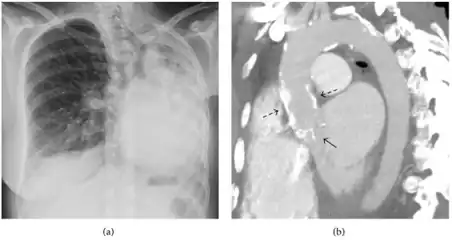

A fibrothorax can typically be diagnosed by taking an appropriate medical history in combination with the use of appropriate imaging techniques such as a plain chest X-ray or CT scan.[1] These imaging techniques can detect fibrothorax and pleural thickening that surround the lungs.[11] The presence of a thickened peel with or without calcification are common features of fibrothorax when imaged.[1] CT scans can more readily differentiate whether pleural thickening is due to extra fat deposition or true pleural thickening than X-rays.[1]

If a fibrothorax is severe, the thickening may restrict the lung on the affected side causing a loss of lung volume.[11] Additionally, the mediastinum may be physically shifted toward the affected side.[1] A reduction in the size of one side of the chest (hemithorax) on an X-ray or CT scan of the chest suggests chronic scarring.[9] Signs of the underlying disease causing the fibrothorax are also occasionally seen on the X-ray.[9] A CT scan may show features similar to those seen on a plain X-ray.[11] Lung function testing typically demonstrates findings consistent with restrictive lung disease.[9]

CXR of an individual affected by fibrothorax (consequence of tuberculosis) -

Extensive left-sided fibrothorax -

Chest radiograph displaying inhomogeneous opacification of the left half of the chest that is fibrothorax -